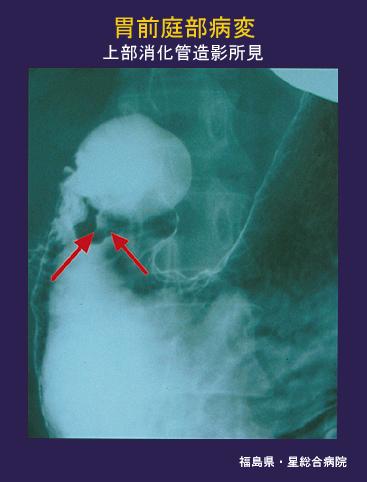

见于遗传性非息肉性大肠癌(HNPCC)的脑肿瘤 (Turcot征候群)

Fukushima Pref., 星综合病院 (Dr. 权田, 野水)

Turcot综合症/

胃(部位)/前庭

X线

0型(表在型)/IIc型(IIc)

肿瘤最大直径

1~9

m